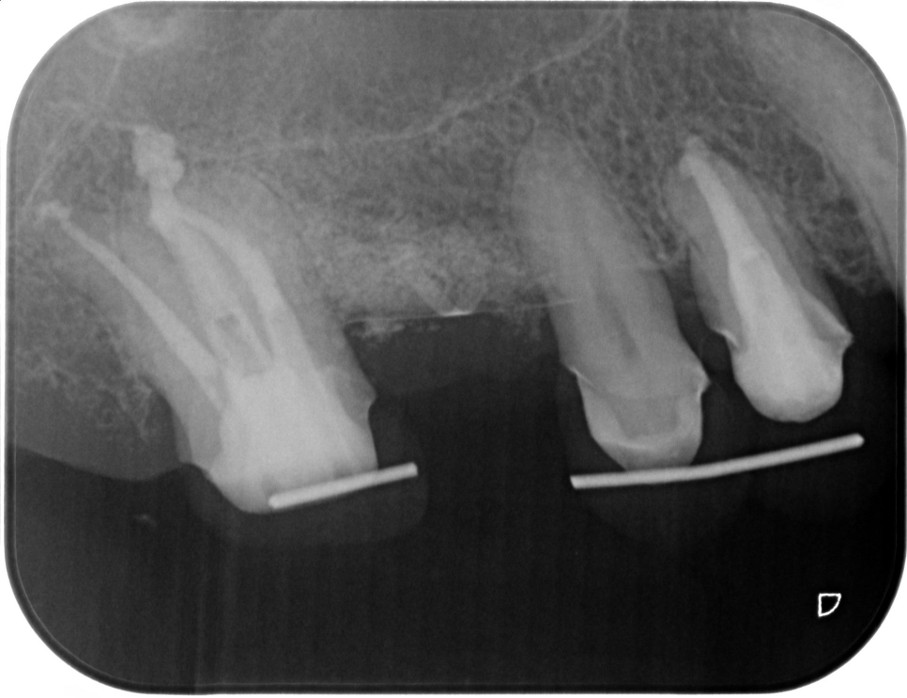

症例3

| 患者様データ | 50代 女性 |

| 来院時の主訴 | 「全て最善の方法で治して健康になりたい。」 |

| 医院の診断 | 虫歯の再発、慢性根尖性歯周炎、炎症による歯髄狭窄、歯根の湾曲、人為的破折ファイルの存在 |

歯髄狭窄+歯根湾曲+破折したファイルの存在が複合した歯でした。 ラバーダム防湿とマイクロスコープを使用して丁寧に治療を行いました。 再根管治療のため、殺菌性があり歯を補強することのできる根管充填材料を使用しています。 |